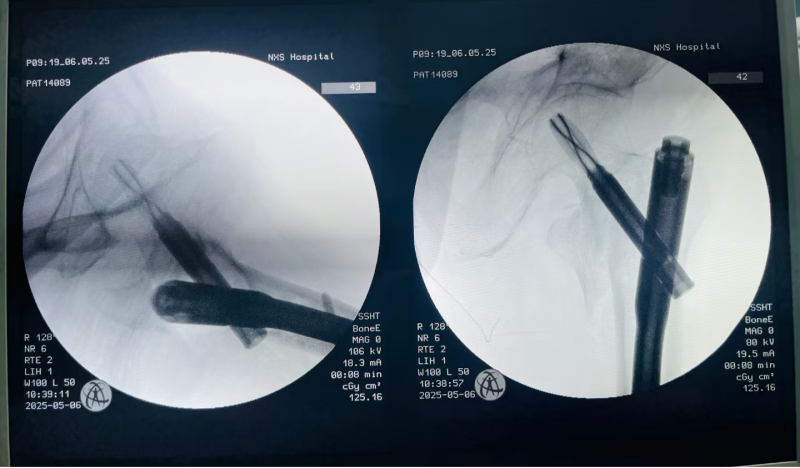

医生为患者实施微创手术

术中骨折完美复位,坚强内固定